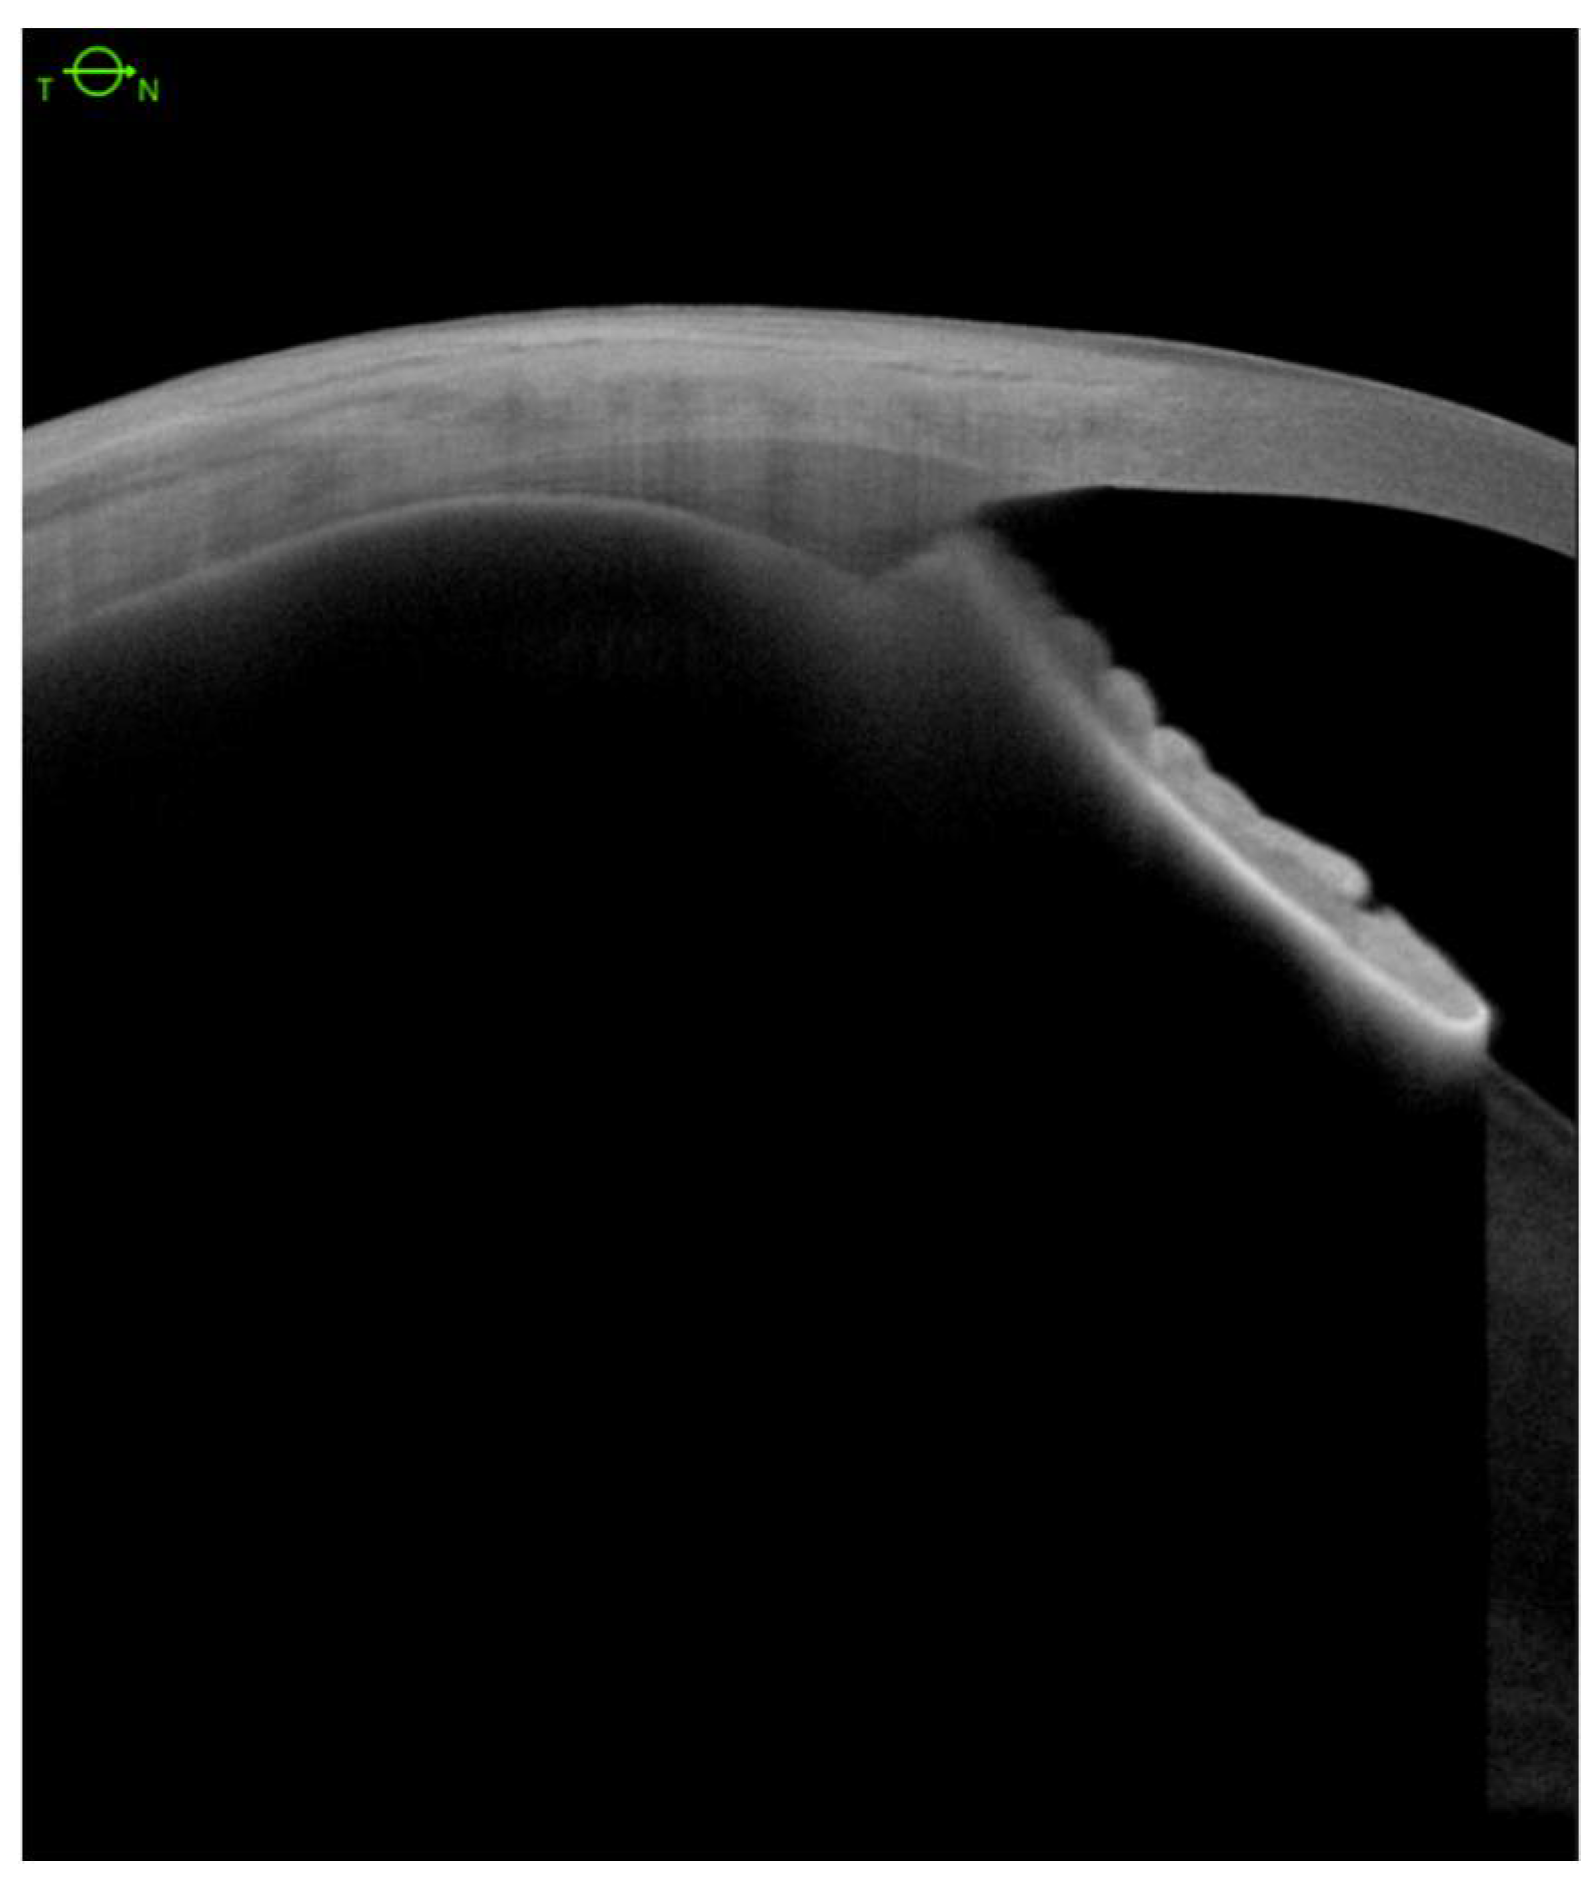

Encircling Scleral Buckling Surgery for Severe Hypotony with Ciliary Body Detachment on Anterior Segment Swept-Source Optical Coherence Tomography: A Case Series

2. Materials and Methods